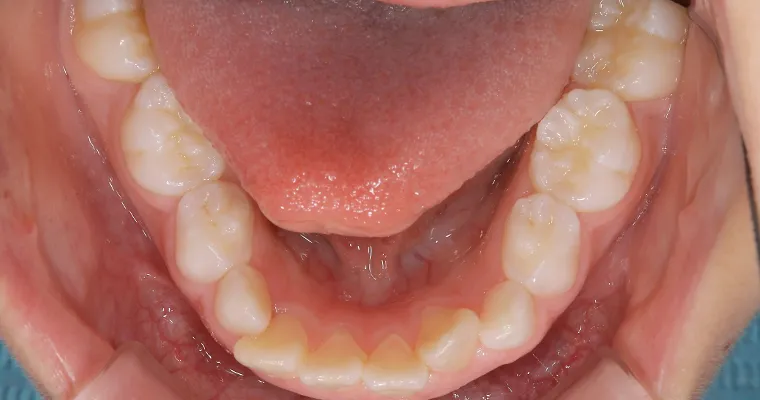

下顎咬合面観

BEFORE

AFTER

| 主訴 | 歯並びが悪い 乳歯と永久歯が重なっている 歯がまっすぐはえてこない |

|---|---|

| 治療期間 | 6-7ヶ月 |

| 治療費 | 440,000円(税込) ※調整、器具、治療後にお渡しするEFLine(矯正後の後戻りを防ぐ器具)も全て込みでの金額となっております。 |

| 治療内容 | 拡大床矯正 EF Lineで筋機能療法 |